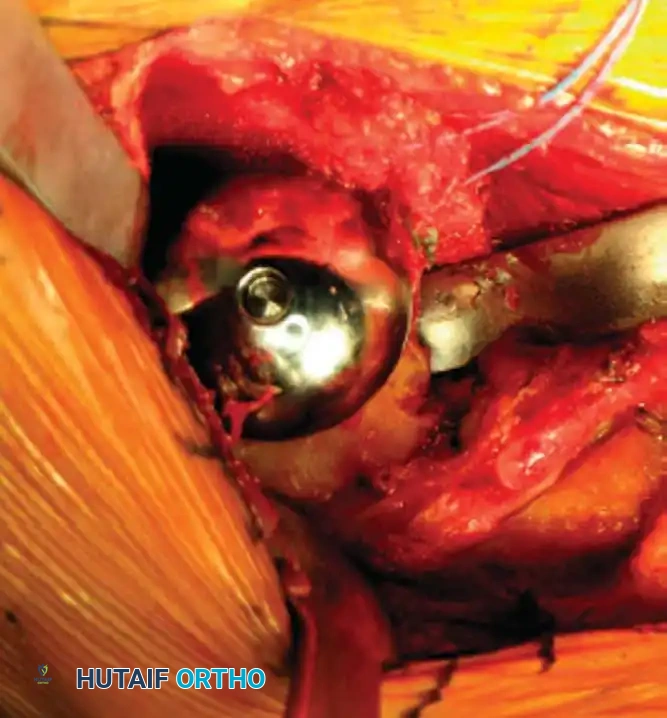

5. Humeral Preparation and Implantation

Broach the humeral canal sequentially. Assess the trial components for stability, ensuring 50% posterior translation on the "drawer test" and no superior escape. Implant the final prosthesis (press-fit or cemented based on bone quality).

Reverse Total Shoulder Arthroplasty (rTSA)

The rTSA fundamentally alters shoulder biomechanics. By medializing and distalizing the center of rotation, it increases the deltoid moment arm and recruits more anterior and posterior deltoid fibers for elevation, bypassing the need for a functional rotator cuff.

Surgical Nuances for rTSA:

* Glenoid Baseplate: Must be positioned inferiorly on the glenoid to avoid scapular notching. A slight inferior tilt (10 degrees) is often utilized.

* Glenosphere: Typically 36 mm or 42 mm. Larger spheres increase stability and range of motion but may increase the risk of notching.

* Humeral Stem: Often placed in 0 to 20 degrees of retroversion.

Clinical Pearl: Tensioning is the most critical step in rTSA. The joint should be stable in all planes. If the joint dislocates easily, a thicker polyethylene insert or a larger glenosphere is required. However, over-tensioning can lead to acromial stress fractures or brachial plexopathy.